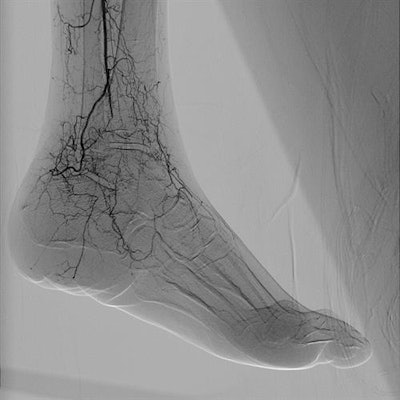

Fine details are visible with the Azurion 7 interventional system. Image courtesy of Philips Healthcare.At its ECR booth, Siemens Healthineers is directing visitors to Multix Impact, a floor-mounted DR system, and Mobilett Elara Max, a mobile x-ray unit. Multix Impact features a height-adjustable, float-top table, as well as an in-room touch-based user interface that enables radiographers to stay at the patient's side during examinations. Key features include graphical organ program selection and a positioning guide display. The device has 17 x 15-inch digital detectors.

Image of prostate cancer embolization acquired with Canon's Alphenix interventional system in 4DCT mode. Image courtesy of Canon Medical Systems.An interventional suite that pairs an angiography system with a CT scanner -- called Alphenix 4D CT -- also is being demonstrated at the vendor's booth. The suite matches an Alphenix Sky + C-arm with an Aquilion One Genesis volumetric CT scanner, enabling clinicians to plan, verify, and treat patients in a single session.